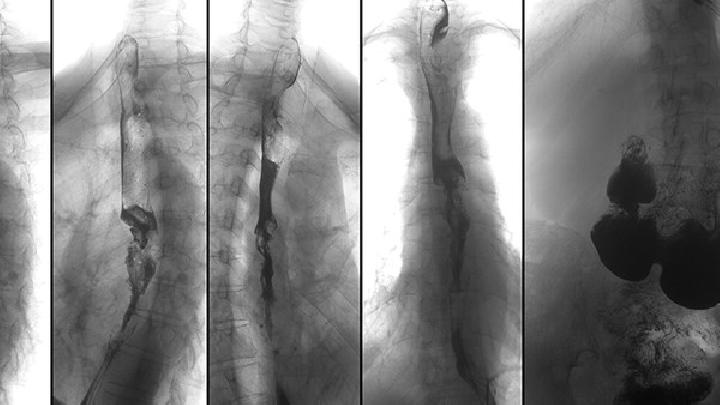

• 脊柱侧弯